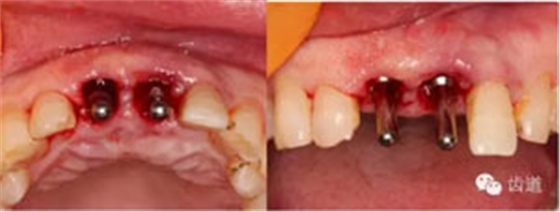

植入種植體(唇側(cè)留2-3mm jumping gap)

確定植入深度(齦下3-4mm)

小直徑愈合基臺(tái)就位后唇側(cè)植骨

更換大直徑愈合基臺(tái)